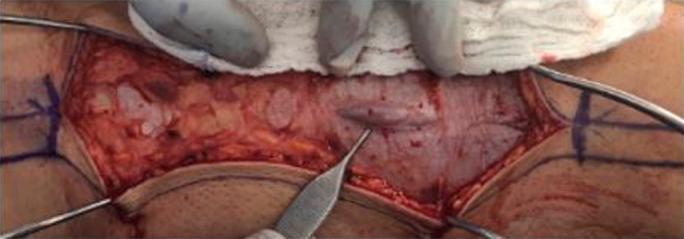

This report describes the case of quadriceps contusion progressing to acute compartment syndrome (ACS) of the thigh. A 17-year-old football player presented the morning after a direct impact injury to the anterior thigh in intractable pain and pain with short arc motion. He was diagnosed with ACS and underwent successful fasciotomy, ultimately returning to play at 4 months.

ACS is rare but potential catastrophic progression of quadriceps contusion. Accurate and timely diagnosis followed by appropriate rehabilitation is necessary for optimal outcomes.